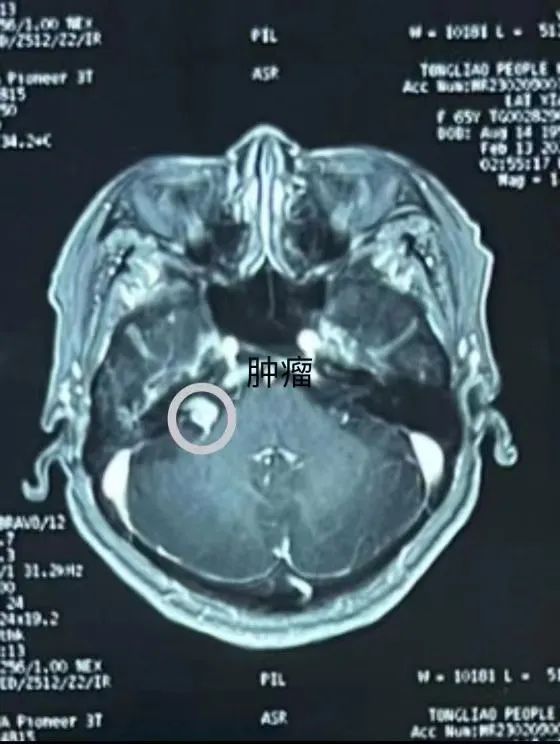

该患因“右耳听力减弱20余年”来我院就诊,经检查诊断为右侧桥小脑角占位,考虑听神经瘤。听神经瘤为颅内神经肿瘤中最多见的一种良性肿瘤,又称前庭神经鞘膜瘤,位于桥小脑角区,此区域曾被称为“血腥三角”,因其特殊生长方式,常常侵犯面神经、三叉神经及后组颅神经,同颅底血管、神经紧密相连,手术难度极高,是神经外科手术中的高难度手术,且术后面瘫发生率高。术前经过神经外科团队讨论研究,赵林主任医师为患者制定了周密、详尽的手术方案,在与患者充分沟通后,决定为其行右侧乙状窦后入路听神经瘤切除手术。

术中可见该患者右侧内听道开口存淡黄色肿物,与前庭神经关系密切,粘连紧密,并向内听道生长,磨除内听道后壁约5mm,显露肿瘤外侧缘,肿瘤内减压及取标本完整切除肿瘤,面神经及前庭神经根保护完好,内听道动脉保留完好。术后右耳听力较术前无明显减弱,无面瘫,现已康复出院。